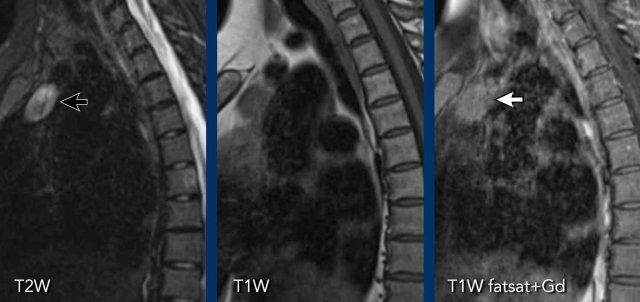

Các hình ảnh này của bệnh nhân nữ 28 tuổi.

Khối trung thất được phát hiện trên CT chụp để tìm thuyên tắc phổi.

Hình ảnh

Có một khối ở khoang trước mạch máu.

Có một số vôi hóa.

Tiếp tục với các hình ảnh MRI…

MRI thể hiện rõ hơn đây là tổn thương hỗn hợp với các thành phần dạng nang (chuỗi xung T2W) và các thành phần đặc có ngấm thuốc.

Không có hiện tượng giảm tín hiệu trên chuỗi xung T1W pha đối lập (out-of-phase).

Chẩn đoán cuối cùng

Kết quả cho thấy đây là u tuyến ức dạng nang.

Mặc dù hầu hết u tuyến ức biểu hiện là khối đặc hình bầu dục có ngấm thuốc, một số trường hợp có thể chứa các thành phần dạng nang và vôi hóa.

Điều này có thể gây khó khăn đáng kể trong việc phân biệt với u quái (teratoma).